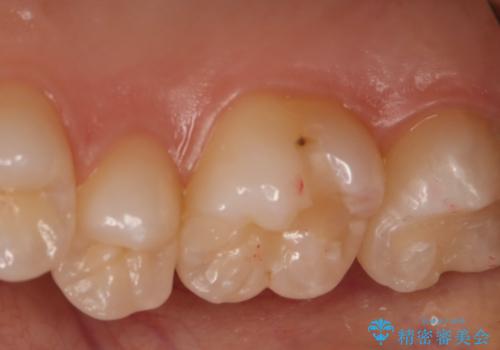

- 右上6番の保険材料で詰められた部分をセラミックにやり変え希望の患者様です。

切削量などを考慮し、セラミックインレーでの治療を選択しました。

う蝕が深くまで進行していたので、全て除去した上でCR裏層を行い形成、印象を行っています。